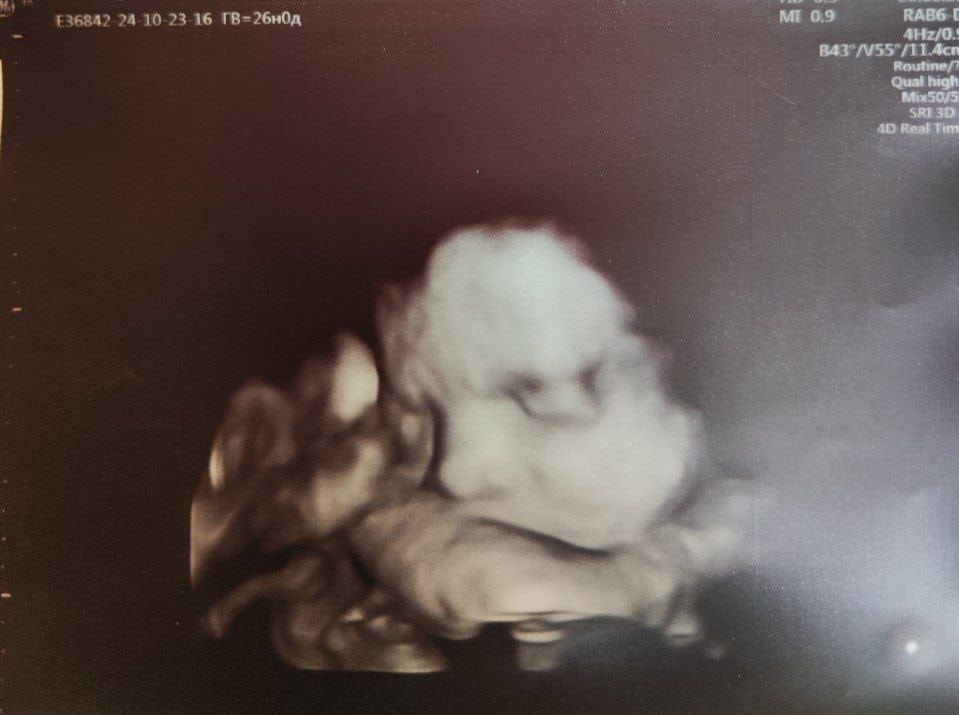

26 недель ровно, папа просто соскучился по малышке (23.10.2025)

Масса 1258г (88 процентиль, опережение на 2.5 недели)

БПР 73мм, ОЖ 248мм, ДБ 53мм

Околоплодные воды несколько больше нормы